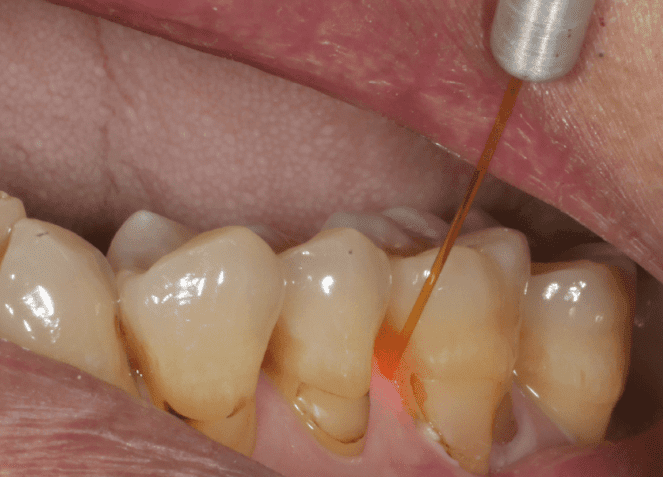

雷射輔助牙結石手術

Er:YAG雷射(2940nm波長)能選擇性作用於結石中的水分,產生微爆裂作用使結石剝離,同時具有殺菌效果。適合對傳統器械敏感的患者,或作為複雜牙周病例的輔助治療。需嚴格控制能量參數(30-50mJ/pulse)以避免牙本質過度熱損傷。